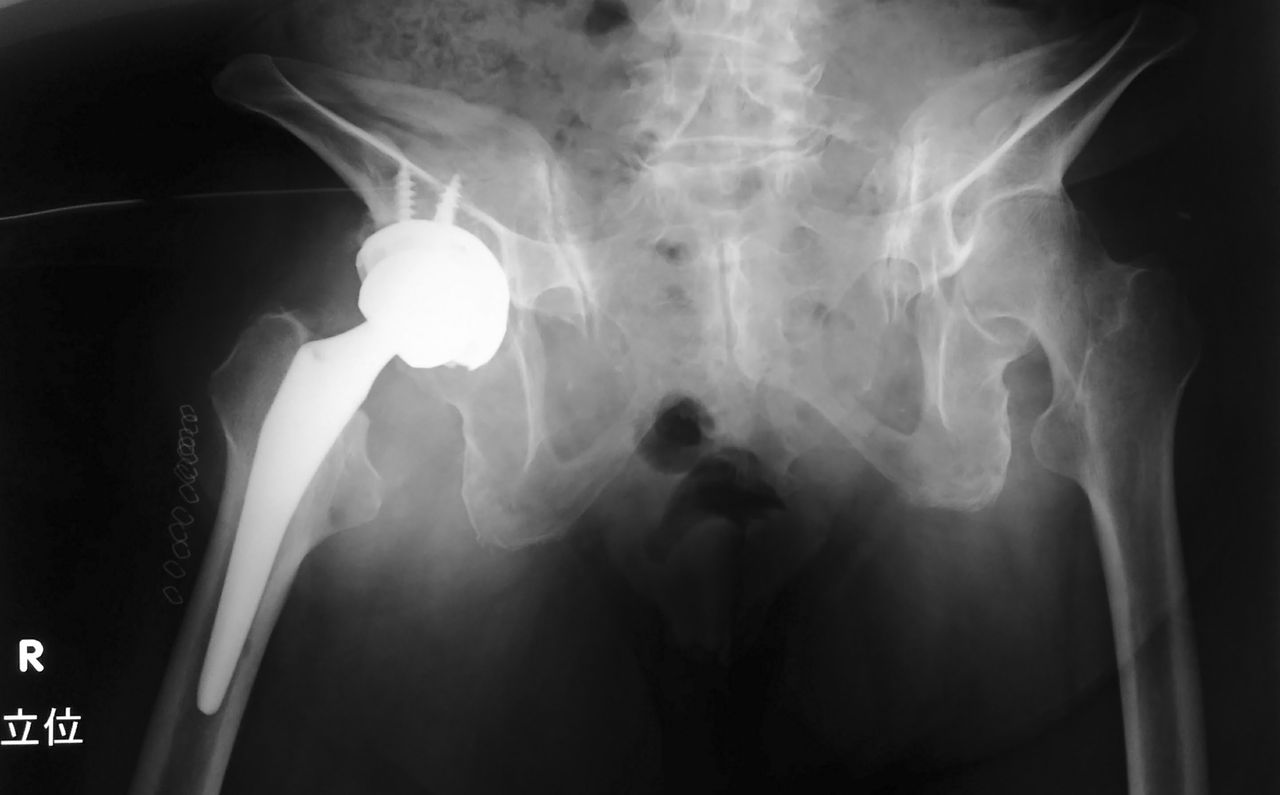

上図は、術後の単純X線像(臥位)です。臥位ではなんの変哲も無い股関節です。カップの外方傾斜角は40度ですが、前方開角はほぼゼロとなっています。

次は、術後の単純X線像(立位)です。見ての通り、強烈な骨盤後傾を認めます。ここまで極端な症例は、さすがに珍しいですね。小骨盤腔が潰れて完全に無くなっています。

そして、肝心のカップなのですが、外方傾斜角は40度で、前方開角もいい感じでついています。目測で前方開角20度ぐらいでしょうか?